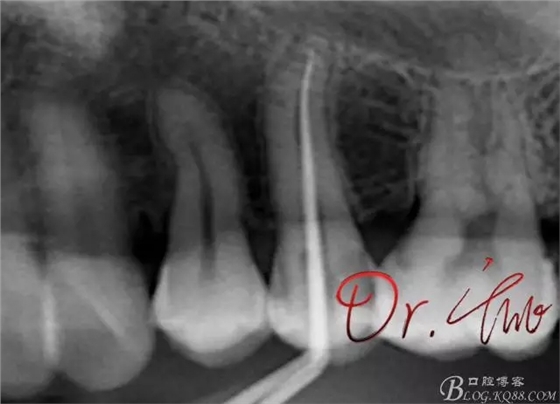

重點第二例病例,初診

拍片確定長度

試主尖,近中頰側(cè)形成臺階

試主尖,近中頰側(cè)再次拍片查看臺階位置及確定長度

試主尖,近中頰側(cè)試主尖,此時手用銼02錐度的已擴到30號,可以明顯感覺到臺階位置,挫預(yù)彎后找好正確位置可順利到達根尖,但是機用銼就是下不去,也是郁悶

試主尖,在30號02錐度K挫到達根尖后,用02錐度牙膠尖找準位置,進行試尖